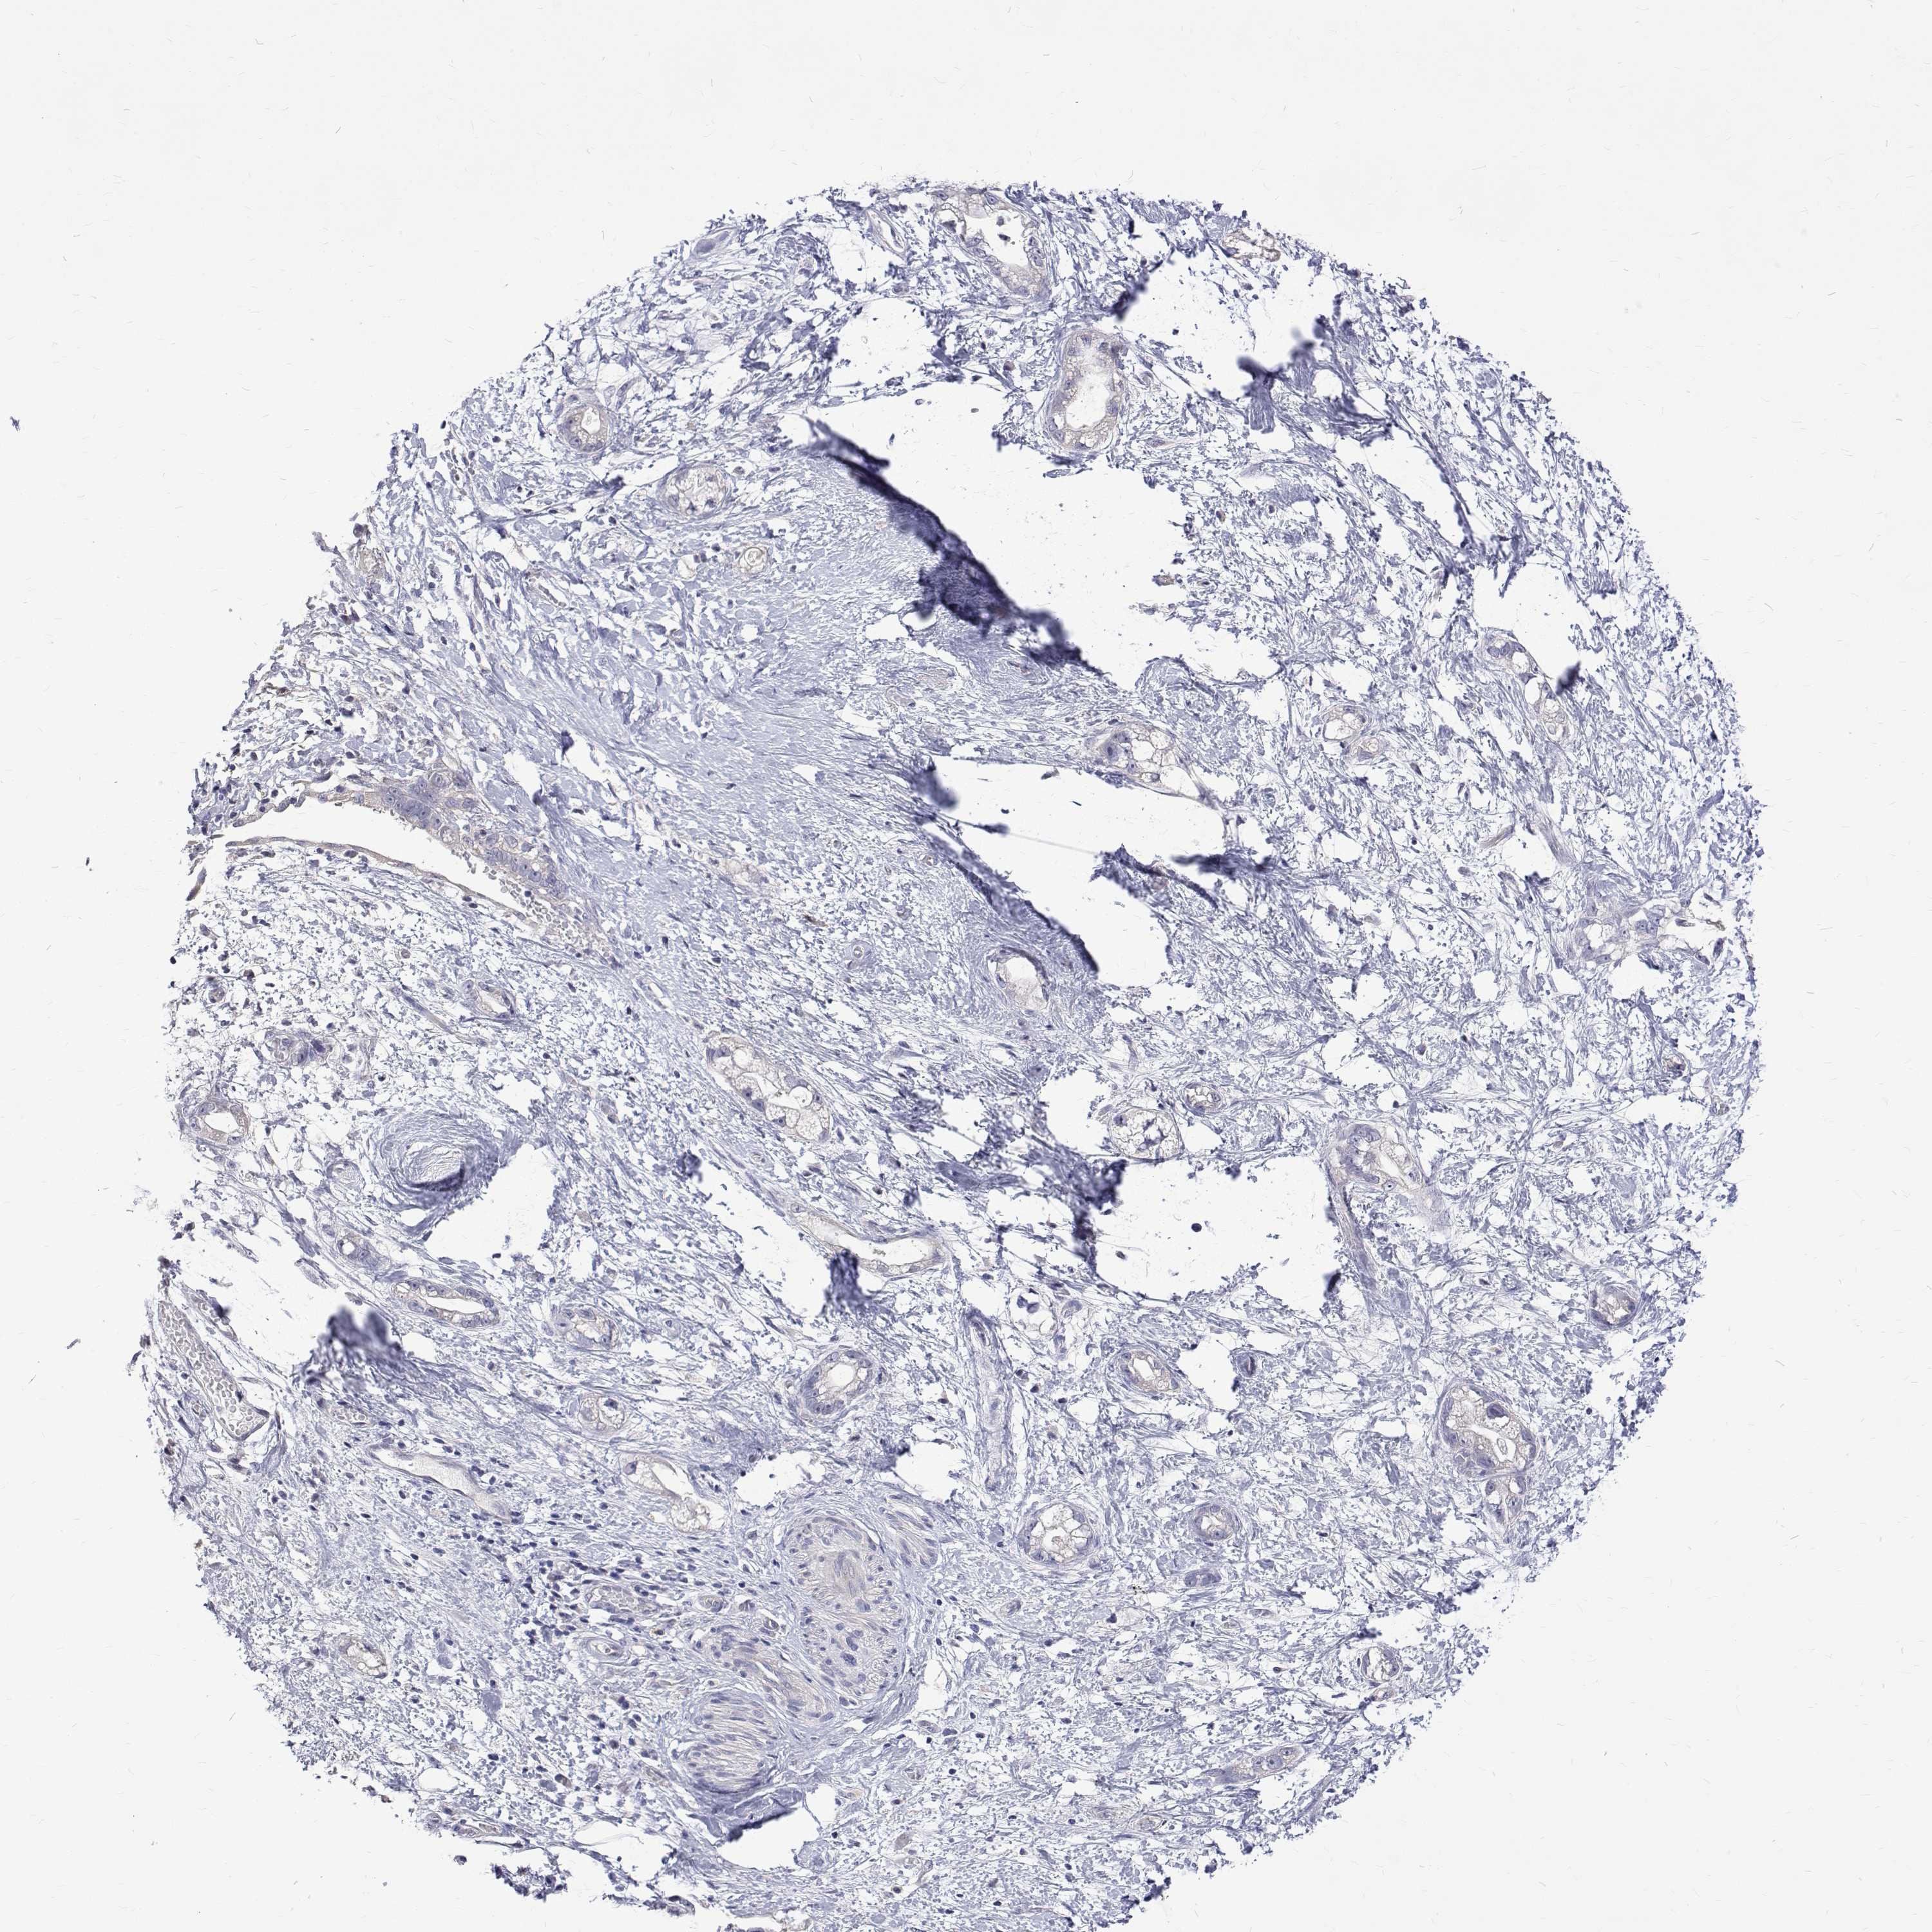

STOMACH CANCER - Protein expressioni

A mouse-over function shows sample information and annotation data. Click on an image to view it in a full screen mode. Samples can be filtered based on level of antibody staining by selecting one or several of the following categories: high, medium, low and not detected. The assay and annotation is described here.

Note that samples used for immunohistochemistry by the Human Protein Atlas do not correspond to samples in the TCGA dataset.

Antibody stainingi

Antibody staining in the annotated cell types in the current human tissue is reported as not detected, low, medium, or high, based on conventional immunohistochemistry profiling in selected tissues. This score is based on the combination of the staining intensity and fraction of stained cells.

Each image is clickable and will lead to virtual microscopy that enables deeper exploration of all samples and also displays staining intensity scores, fraction scores and subcellular localization as well as patient and tissue information for each sample.

Antibody HPA062294

Staining

High

Medium

Low

Not detected

Intensity

Strong

Moderate

Weak

Negative

Quantity

>75%

75%-25%

<25%

None

Location

Nuclear

Cytoplasmic/membranous

Cytoplasmic/membranous,nuclear

Adenocarcinoma, NOS